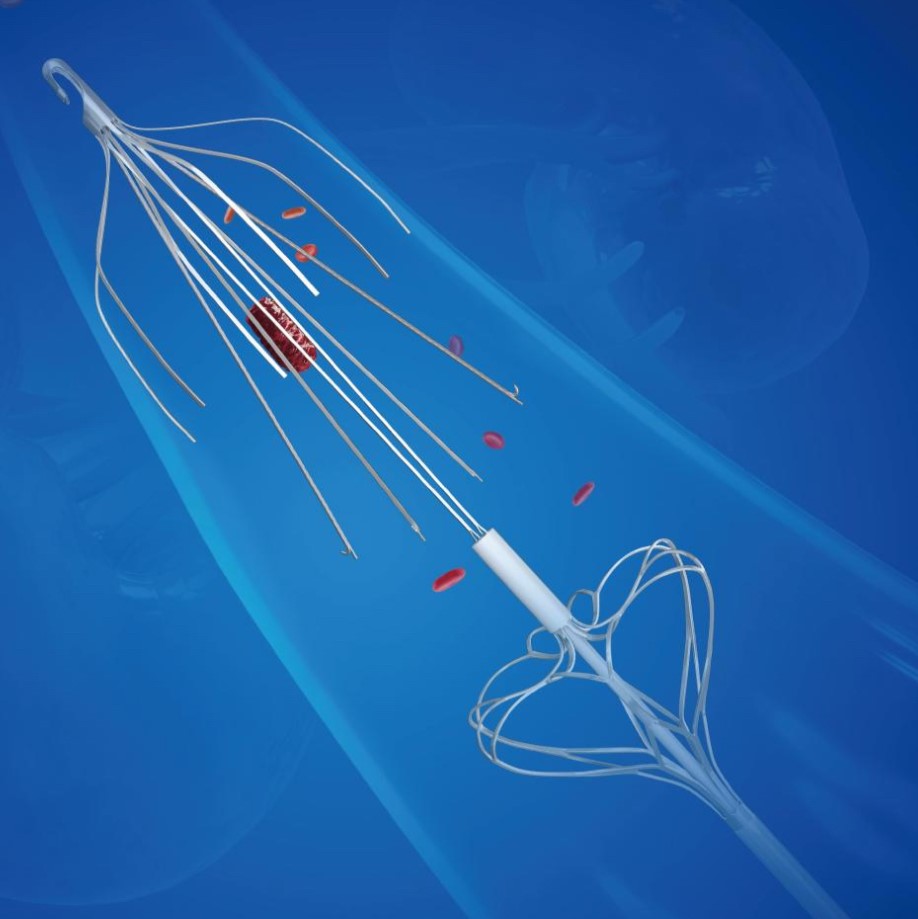

产品介绍

Vewatch®/海神盾™腔静脉滤器通过经股静脉或经颈静脉入路经皮置入,用于预防下腔静脉系统栓子脱落而引起的肺动脉栓塞(PE)。包括:1.已经发生PE或下腔静脉及髂、股、腘静脉血栓形成的患者有下述情况之一者:(1)存在抗凝治疗禁忌证者;(2)抗凝治疗过程中发生出血等并发症;(3)充分的抗凝治疗后仍复发PE和各种原因不能达到充分抗凝者。2.PE,同时存在下肢深静脉血栓形成者。3.髂、股静脉或下腔静脉内有游离漂浮血栓或大量血栓。4.诊断为易栓症且反复发生PE者。5.急性下肢深静脉血栓形成,欲行经导管溶栓和血栓清除者。